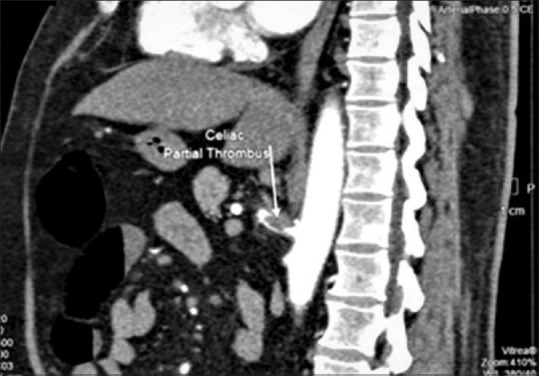

Mesenteric vascular thrombosis, typically of the superior mesenteric artery, is a frequent occurrence in patients with hypercoagulable conditions. Isolated involvement of the celiac artery is rare. Patients with celiac artery thrombosis can present with an acute abdomen or occasionally with acid peptic symptoms. A delay in diagnosis is associated with high rates of morbidity and mortality. We present a rare case of splenic infarction with celiac trunk thrombosis in a 54-year-old patient with underlying antiphospholipid (APLA) syndrome who presented with epigastric pain that was mistaken for symptoms of acid reflux.

Abstract Image